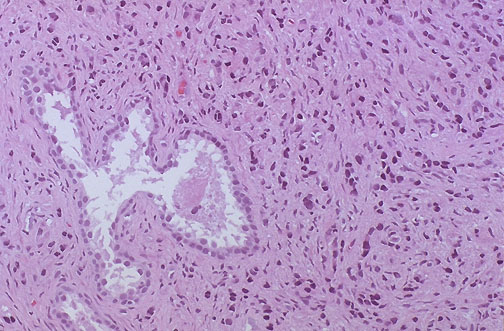

This is a high grade adenocarcinoma of prostate with single infiltrating cells. A residula normal prostatic gland is seen at the left of center.